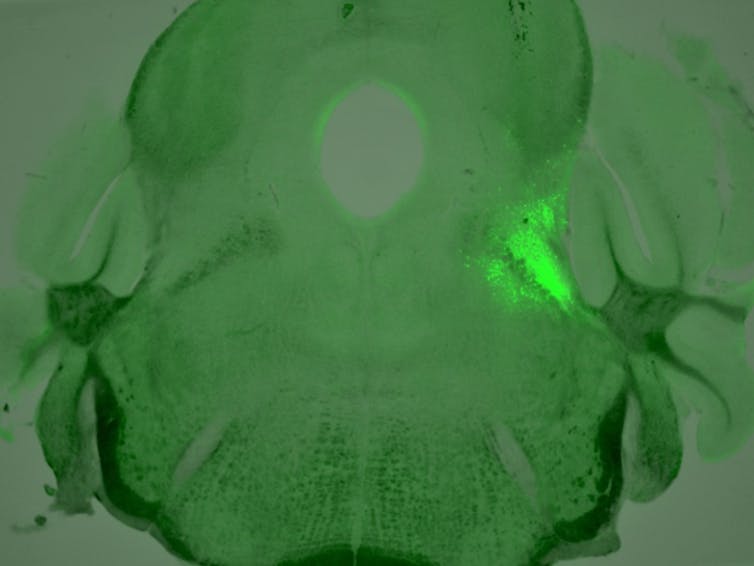

A cluster of neurons with highly active opioid receptors, highlighted in neon green, is located in a small area of the mouse brainstem called the lateral parabrachial nucleus.Salk Institute, CC BY-NC-NDSearching through a public database of gene expression patterns, or how genetic material is translated into proteins that let cells function, in the mouse brain, we serendipitously found that one type of opioid receptor called the µ-opioid receptor is highly expressed in parabrachial neurons.

Previous studies have shown that the effects opioids have on the body are mainly mediated by µ-opioid receptors. We therefore focused our investigation on how pain and breathing interact with each other in neurons that express these receptors.